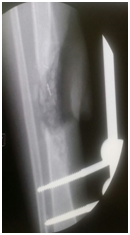

Three month later, the external fixator was removed; back slab was applied for 10 day to decrease the possibility of pin site infection. Final augmentation of the grafting was done by fibular allograft and fixed by 12 whole LCP. The nerve grafting performed (Figures 5a-5c). Two months later, the patient was seen in the clinic, he was able to move his ankle, radiography of the tibia demonstrated a remarkable filling of the gap by bone (Figures 6a-6d).

• Figure 5a-c During fixation of the tibia with DCP plate and insertion of fibular graft and grafton.